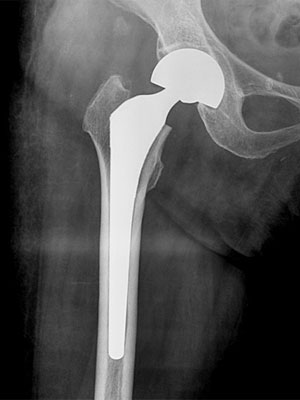

全人工股関節置換術

手術後、約2、3日後より、立位訓練等のリハビリを実施していき、深部静脈血栓症予防や股関節周囲筋群の強化、脱臼防止を指導していきます。

手術前

手術後

骨折後の手術例

股関節頚部内側骨折(人工骨頭)